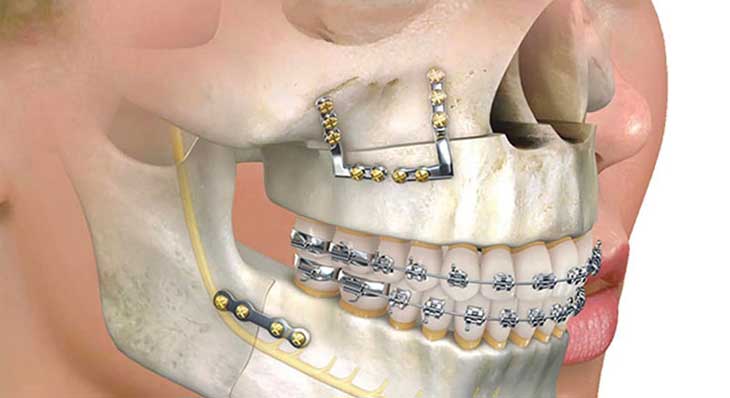

◦ انجام جراحی: جراحی در بیمارستان و تحت بیهوشی کامل انجام می شود. جراح با ایجاد برش هایی از داخل دهان، استخوان های فک را جابجا کرده و در موقعیت جدید با صفحات و پیچ های کوچک تیتانیومی ثابت می کند.